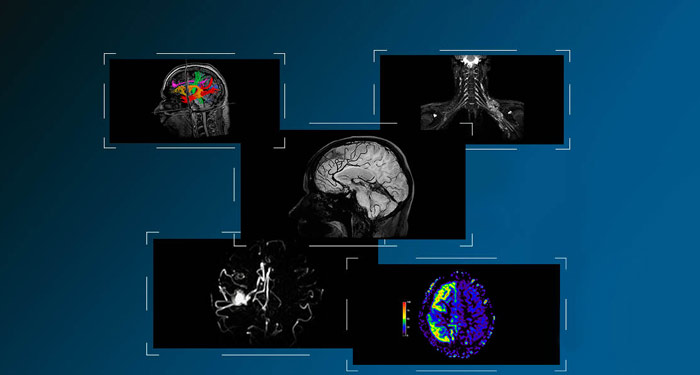

![MR Neuro Imaging]()

Damit mehr Patienten von der Magnetresonanztomographie profitieren, erfahren Sie hier mehr über neue neurologische Anwendungen von Philips Healthcare.